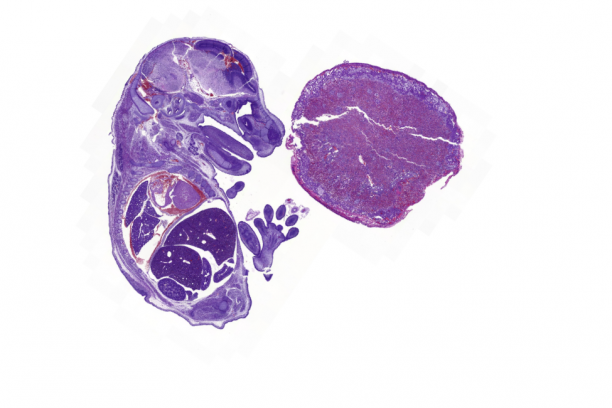

- Comprehensive, state of the art diagnostic, necropsy and comparative pathology services for animal model systems with specific expertise and focus on mouse models

- Automated tissue micro-array preparation